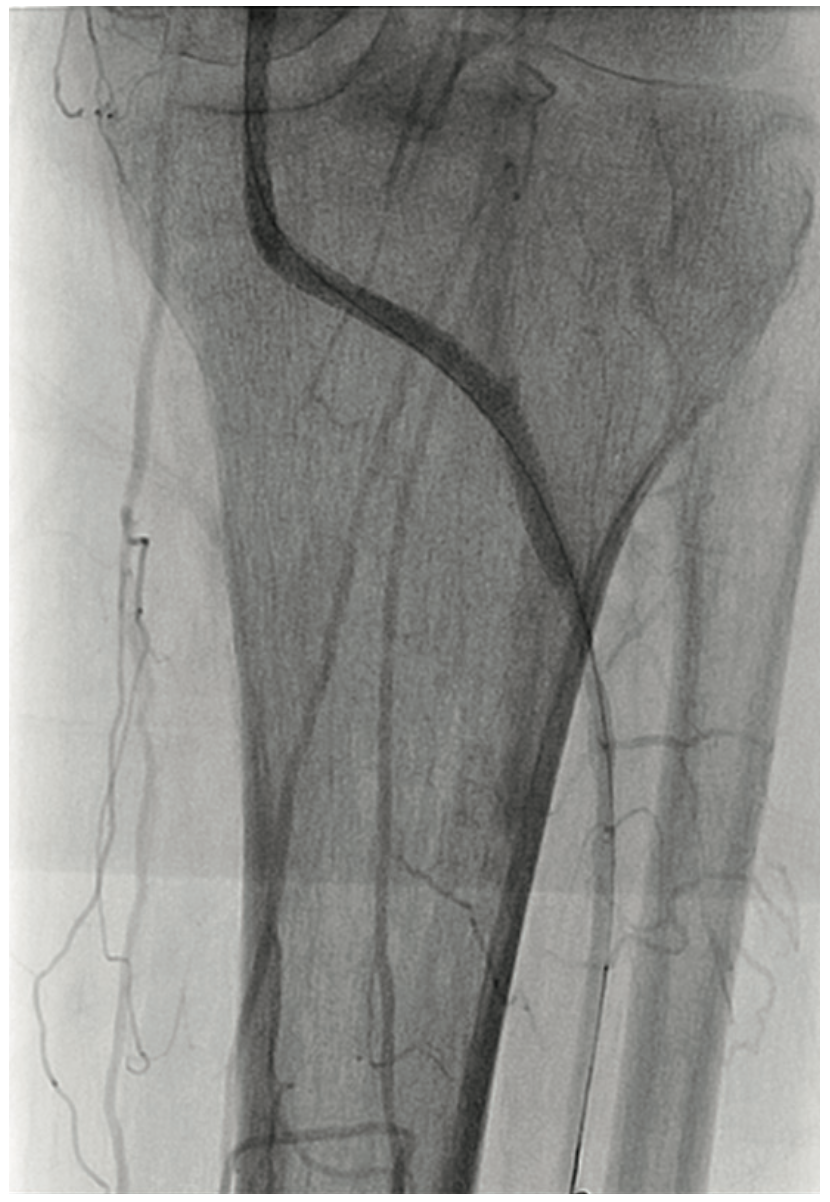

A 63-year-old male smoker presented with critical limb ischemia of his left foot. Four years prior, the patient underwent right fem-pop bypass after failed intervention on his right leg. He ended up losing the fifth digit on his right foot. Three years prior to his visit, he underwent a fem-pop bypass procedure on his left leg for severe claudication after failed intervention. One year later, he underwent a redo fem-pop on his left leg with a cadaveric vein. Twelve months prior to the visit, a self-expanding stent was placed in that fem-pop graft because of continued foot ischemia. Seven months prior to his visit, his symptoms re-occurred, and the patient was told nothing could be done after an angiogram showed the vessel was occluded. The patient suffered from polyneuropathy and was unable to walk, but did not want amputation. The patient was on cilastazol and coumadin, and had type II diabetes mellitus. His exam revealed a cool and red left foot, but no ulcers. Capillary filling was adequate. The right dorsalis pedis was normal, and there was no popliteal pulse on either side and no left pedal pulses. A contralateral approach was utilized and revealed the graft was occluded on the left side (Figure 1). The patient likely had thrombus in the graft, and we felt that a laser would be appropriate, used either in the traditional manner or with the step-by-step method. Whenever the step-by-step method is utilized, we use the CrossLock LP device (Radius Medical) for centering (Figure 2). The CrossLock LP is usually utilized for infrapopliteal lesions, but in this case, the 3 mm elastomeric balloon would fit well into the nub of the bypass graft. We immediately subtended the bypass graft all the way down and then were able to access the infrapopliteal vessels (Figures 3-4). We performed .9 mm laser (Spectranetics) in the graft and balloon angioplasty (Figure 5). Two Xience stents (Abbott Vascular) were placed, a 4.0 cm and 3.5 cm, at the anastomosis site, and because of residual stenosis at the popliteal, we placed a 5.5 cm Supera stent (Abbott Vascular). Due to multiple failures of the graft, the graft was covered with a 6.0 mm x 250 mm Gore Viabahn stent graft (W.L. Gore & Associates). At the end of the procedure, we were able to achieve brisk 2-vessel runoff (Figures 6-7). Fluoroscopic time was long at 73 minutes and the contrast utilization was 236 mL.